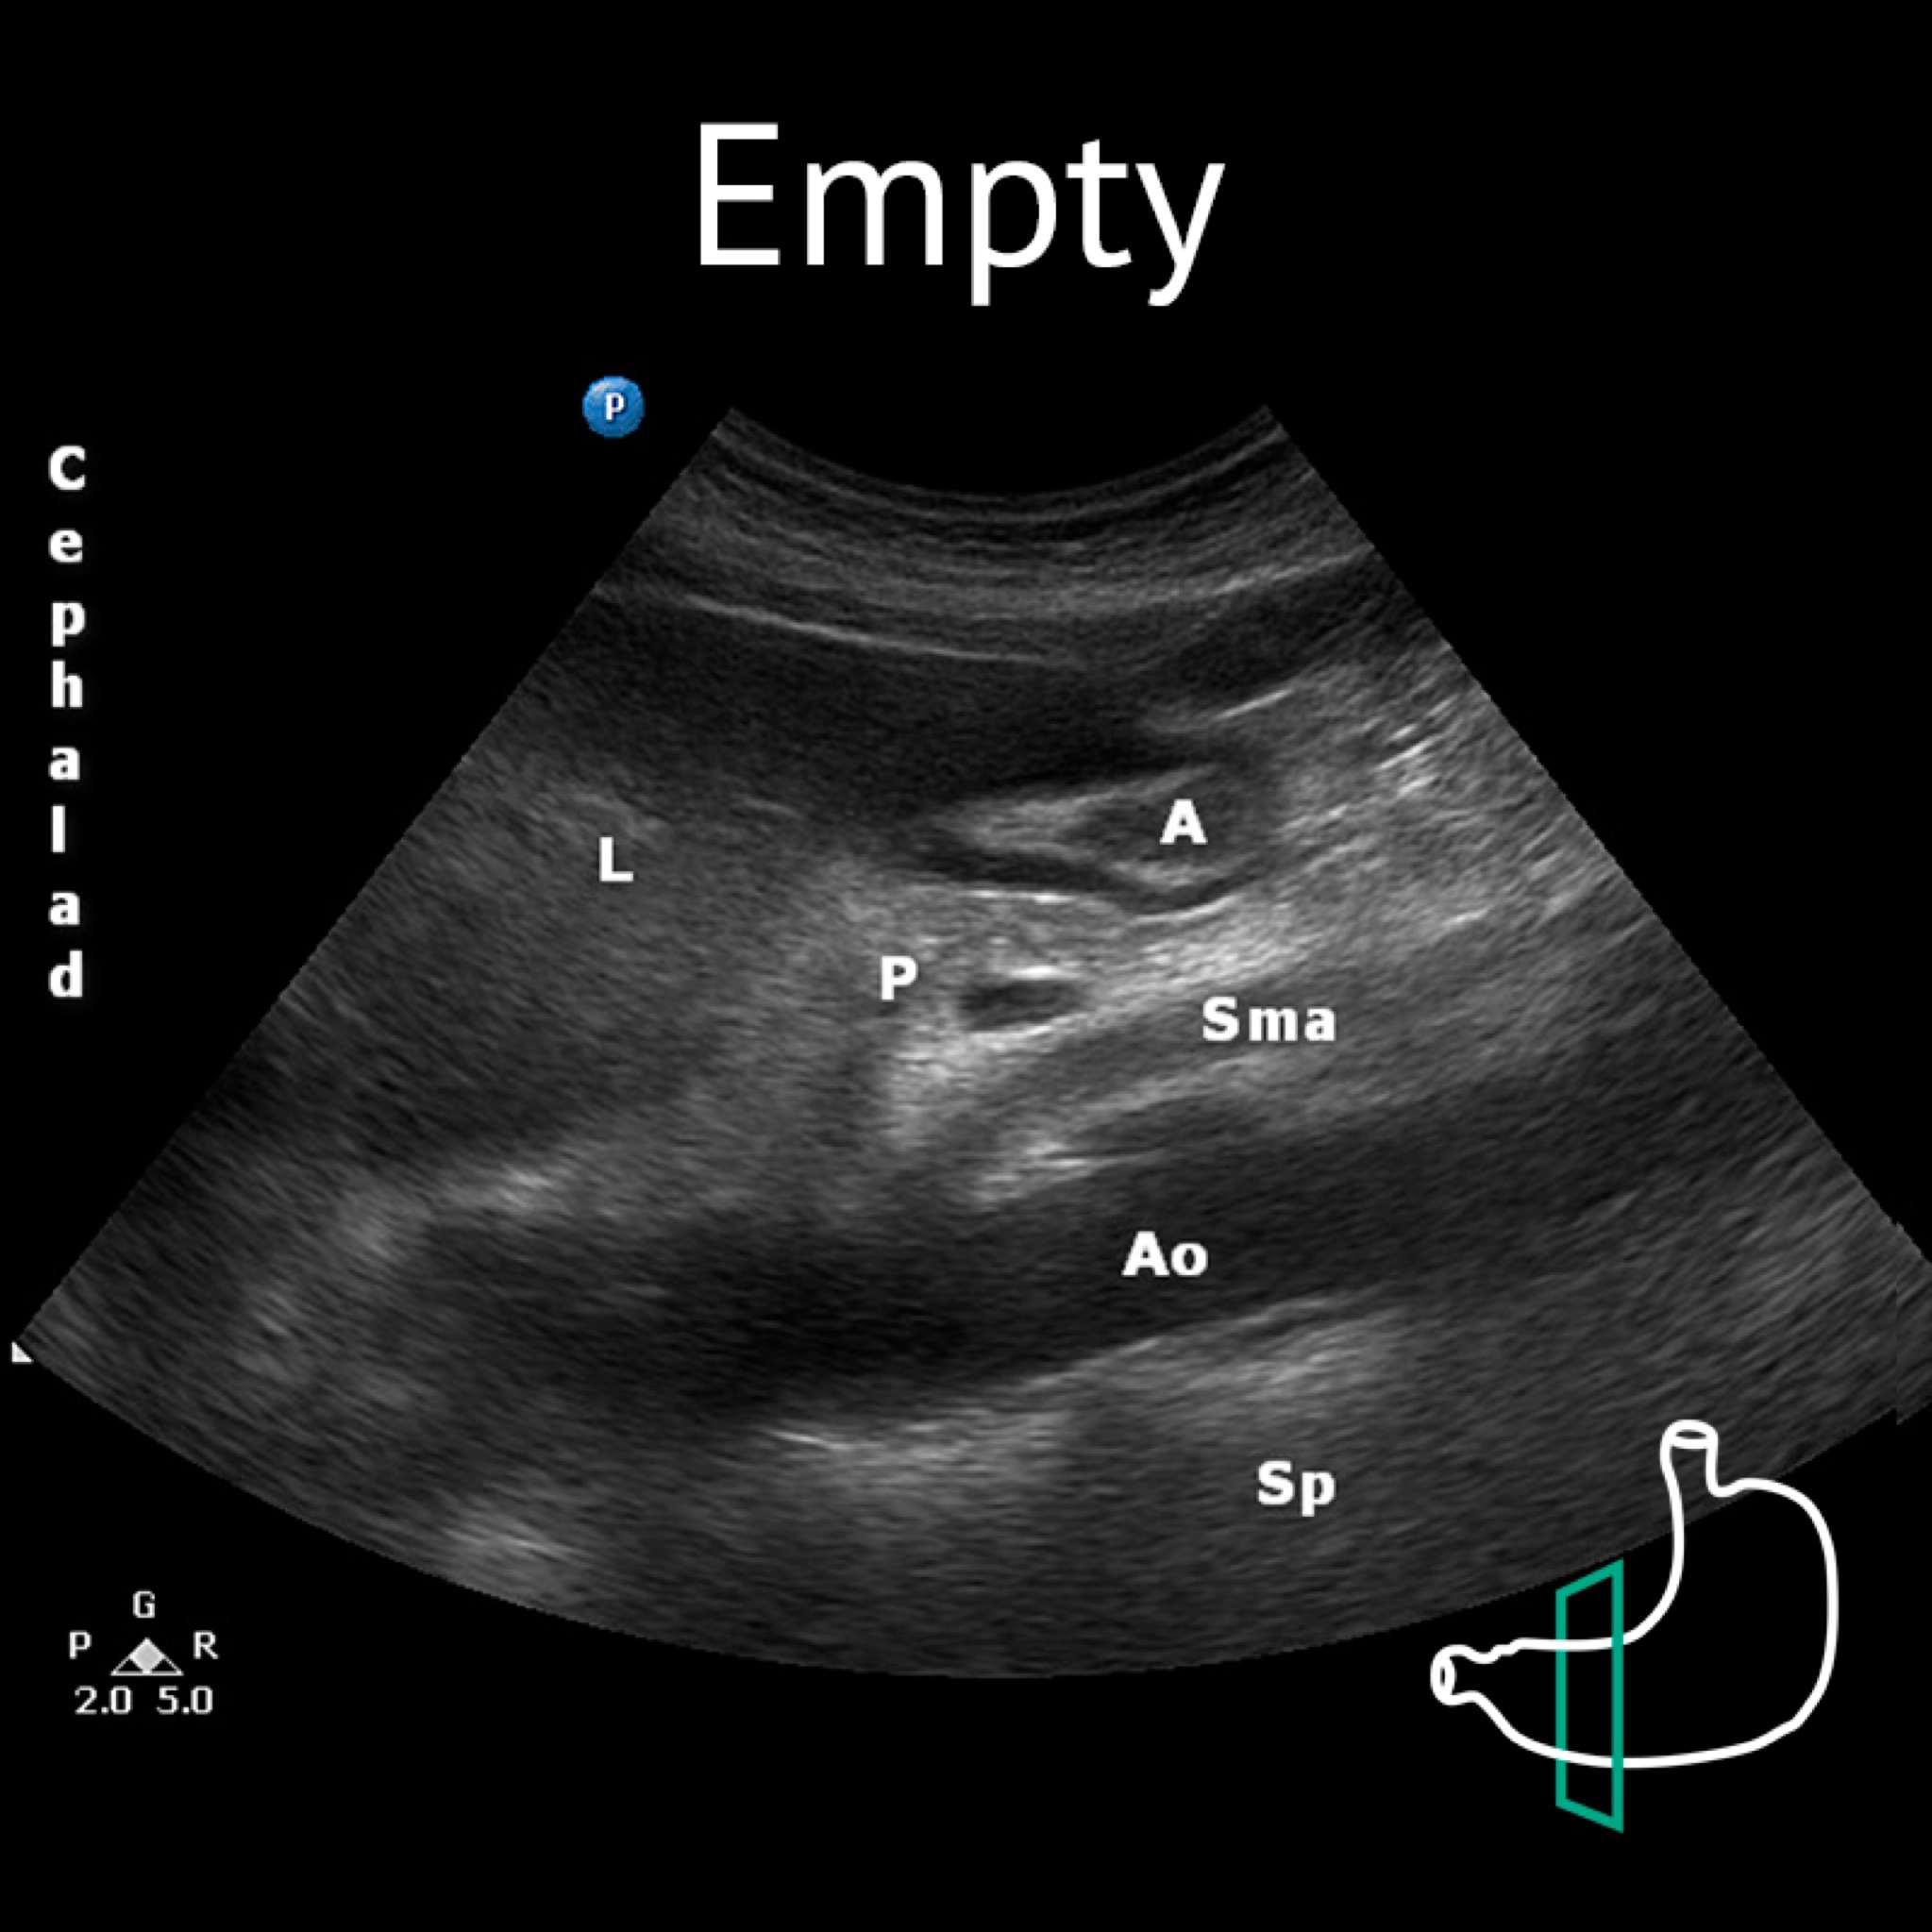

A: antrum; Ao: aorta; L: liver; P: pancreas; Sma: superior mesenteric artery

A: antrum; Ao: aorta; L: liver; P: pancreas; Sma: superior mesenteric artery; Sp: spine